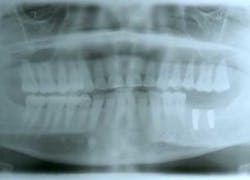

Ten months after the GBR procedure was done, a new panoramic radiograph (Fig. 4) was taken and the site was reentered for implant placement into an ideal restorative position. Dental implants (nobel active 5.0 x 11.5 mm) were placed at the No. 18 and No. 19 positions (Fig. 5), into excellent type I dense bone; note that the majority of the dental implants are completely housed in newly grafted bone. Additional minor bone grafting was done using autogenous coagulum collected during the osteotomies and a xenograft particulate (Bio-Oss, Geistlich), then covered with a resorbable collagen membrane (Biogide, Geistlich) in order to maintain buccal bone stability and contour (Fig. 6). The implants were later uncovered, ensuring that an adequate zone of keratinized tissue was present and the implants were subsequently restored (Figs. 7, 8). The success of this case was dependent upon proper treatment planning, meticulous surgical techniques, patient compliance, and understanding bone and soft-tissue biology.

Fig. 4